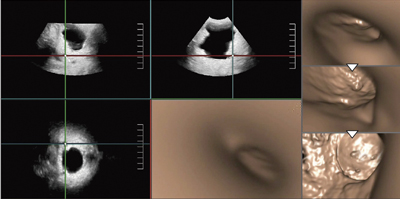

図4は,胆管がんのステント留置症例だが,Fly Thruでは留置されたダブルピッグテイルステントの形状を認識できる精度がある。視点は,末梢からステントへ移動するが,ピッグテイルステントの先端の輪の部分を観察できる。

図4 胆管がんステント留置症例のFly Thru画像 (ステントをくぐり末梢へ) (動画)